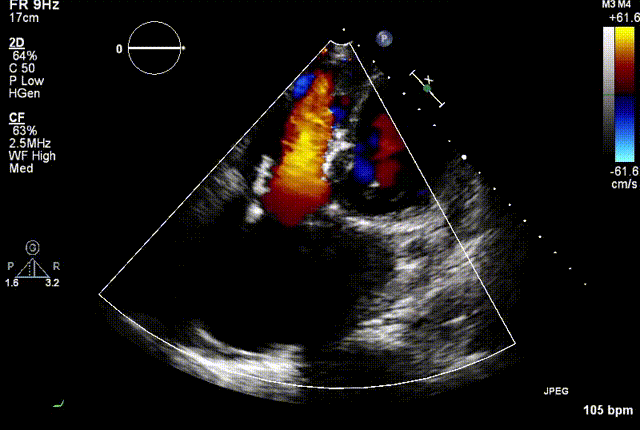

两例患者是都是外科手术高危的极重度三尖瓣反流的老年女性,反复下肢水肿、腹胀、纳差,活动耐力减退。一例患者风湿性心脏病,二尖瓣生物瓣置换术后,房颤,心超显示三尖瓣极重度反流(最大反流宽度15mm);另一例患者房颤,心超示三尖瓣极重度反流(最大流宽度23mm)。

结合术前CT评估结果,葛均波院士团队最终决定选用LuX-Valve Plus 50mm和55mm两种型号的瓣膜,并于2021年11月30日顺利完成LuX-Valve Plus经血管三尖瓣置换术,手术室即刻拔除气管插管,术后第二天转出心内科监护室,下床活动。术后患者三尖瓣反流症状得到显著改善,复查心超结果显示人工三尖瓣瓣膜支架固定稳定,瓣叶关闭形态未见异常,未见明显反流。

复查心超图

在本次救治性临床研究中,治疗的两例患者病因不同解剖结构复杂,均为极重度三尖瓣反流,手术最终都顺利植入了LuX-Valve Plus三尖瓣人工瓣膜。术后超声显示瓣膜支架固定稳定,反流症状显著改善,取得了良好临床治疗效果。